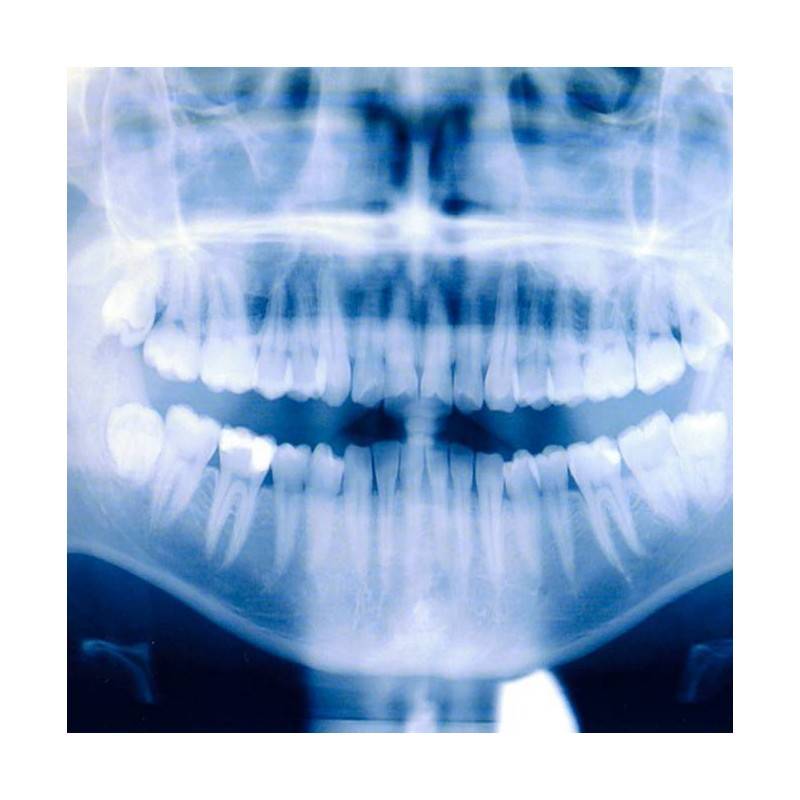

Visita con el especialista en Cirugía maxilofacial. Si es la primera vez que acude, el médico realizará un diagnóstico y pondrá el tratamiento indicado a la patología que presente, ya sea de cara (boca, dientes o cabeza) o de cuello. También se le realizará una ortopantomografía, es una radiografía panorámica en la que se ven los maxilares, la mandíbula y los dientes. Tiene una gran importancia en el diagnóstico odontológico, tanto en cirugía bucal, implantología, ortodoncia, periodoncia y en patología oral y dental.